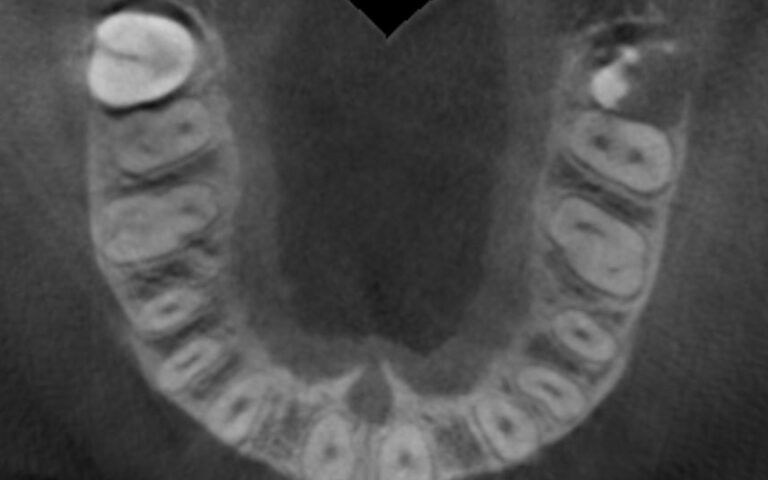

Patient’s initial CT scan after orthodontic treatment Patient’s initial CT scan after orthodontic treatment Patient’s initial CT scan after orthodontic treatment

After this time a CBCT was taken of the maxilla to start planning the surgery for the placement of two implants in positions 12 and 22. During the analysis of the x-ray images, as the measurements indicate, it was observed that the mesio-distal space between 11-13 and 21-23 was limited, which would impede the placement of two standard implants with a diameter of 3.3 mm.